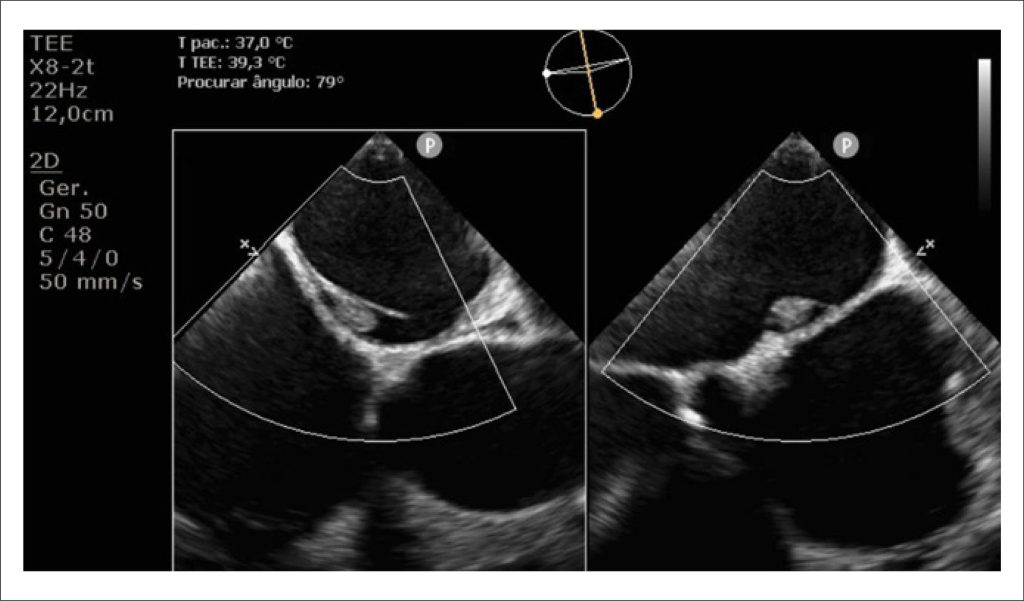

A 59-year-old male patient with a history of systemic arterial hypertension was admitted to the emergency department with a seven-day history of chest pain and palpitations. On examination, he was hypotensive (93/70 mmHg) and tachycardic (150 bpm). A prominent systolic–diastolic murmur was heard along the right upper sternal border.

The initial investigation included electrocardiography (ECG) and Transthoracic Echocardiography (TTE). The ECG revealed atrial flutter, and the TTE showed biventricular dilation [Left Ventricular (LV) end-diastolic/end-systolic diameters: 60/51 mm; right ventricular (RV) basal diameter: 54 mm] and severe systolic dysfunction (LV ejection fraction: 19%; RV fractional area change: 16%). Additionally, a bicuspid aortic valve with mixed disease was identified: low-flow, low-gradient aortic stenosis (peak velocity: 3.1 m/s; peak/mean gradients: 39/23 mmHg; velocity ratio: 0.15; valve area: 0.7 cm, stroke volume index: 17 ml/m) and severe aortic regurgitation (pressure half-time: 170 ms; holodiastolic reversal in the descending aorta, end-diastolic velocity: 24 cm/s).